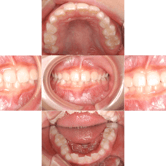

Maloclusión Clase I

La maloclusión Clase I es una alineación incorrecta de los dientes donde la mordida es normal, pero los dientes pueden estar apiñados, espaciados o torcidos.

Los pacientes pueden notar que sus dientes están torcidos o que tienen espacios entre ellos.

Es importante corregir esta condición para mejorar la función y la estética dental.